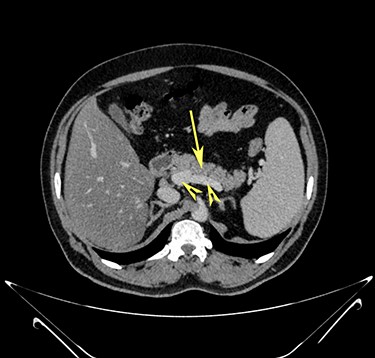

Transverse section image of a contrast-enhanced CT scan of the abdomen at the level 3–3 (Fig. 1), showing a solitary cyst (arrow) with a non-enhancing wall separate from the intestines.